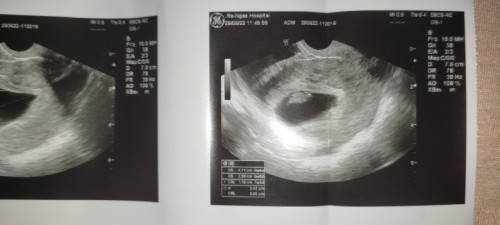

คุณแม่บ้านไหนบ้าง11w มีเลือดออกในช่องคลอดนิดๆไม่ออกเยอะซาวด์แล้วเห็นแบบนี้น้องยังยุวรึป่าวคะ

ก้อนเล็กๆตรงไหนคะแม่ถ้าก้อนเล็กๆในวงดำนั่นคือตัวน้องนะคะ

รูปบ้านนี้ไปฝากท้องตอน11สัปดาห์ค่ะ

ภาพนี้ตอน11w ตอนี้น้องได้18wเเล้วจ้า